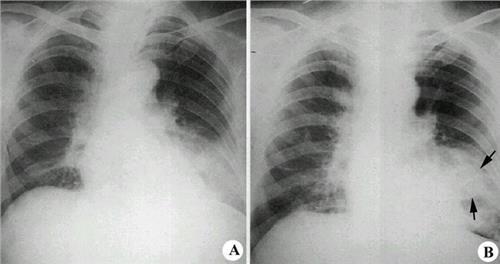

间质性肺炎 双肺纹理增多,混 乱,以双下肺野为 主,部分呈网状

正常胸片 间质性肺炎